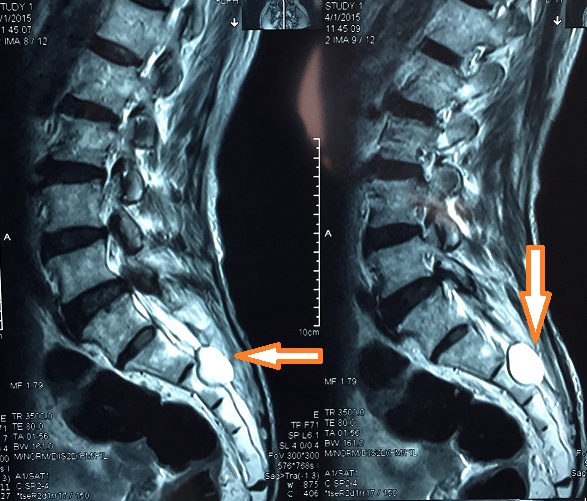

近日,重庆医科大学附属第一医院神经外科接诊一位主诉为“腰椎间盘突出、腰腿疼痛”经诊断,患者并非腰椎间盘突出,而是骶管囊肿。

骶管囊肿属于硬脊膜囊肿,起源于脊髓被膜,故用“椎管内脊膜囊肿”来总称这类疾病,患者主要症状表现为尿频尿胀、会阴区不适、腰骶、坐骨神酸痛等类似腰椎间盘突出的症状。

五、该怎么区分骶管囊肿和腰椎间盘突出症状?

当然,从症状区分两种疾病,即便是对医生都是较难的,真正要确诊多数时候需要借助影像学检查。